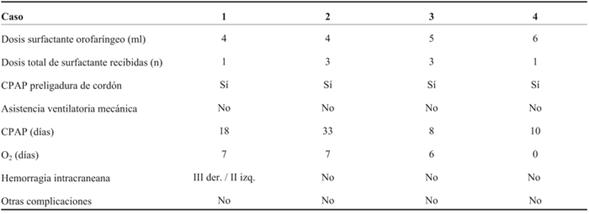

A continuación se detalla la experiencia de los primeros cuatro casos realizados (el primer caso fue el 29 de setiembre de 2017). Contamos con la aprobación del protocolo del Comité de Ética del hospital y con el consentimiento informado y firmado de los padres.

Caso 1

RN, sexo masculino, 1.050 g, nacido a las 27 semanas de edad gestacional (EG) por vía vaginal. El nacimiento vaginal espontáneo ocurrió 60 horas después de la rotura prematura y prolongada de las membranas ovulares, habiendo completado previamente el curso completo de corticoides para la maduración pulmonar fetal. Inmediatamente después del nacimiento, el RN fue colocado en la pared abdominal materna en una bolsa plástica, manteniendo la circulación fetoplacentaria. Simultáneamente, un operador, en este caso residente de Neonatología, administró un bolo de 5 ml de Survanta® (previamente cargado en la jeringa y llevado a temperatura ambiente) con una sonda de alimentación orofaríngea colocada en la hipofaringe antes del inicio de la respiración del RN. Al mismo tiempo, se colocó la pieza nasal para administrar presión positiva continua en la vía aérea. Este procedimiento tomó los primeros 5 segundos de vida, lo cual fue calculado según análisis de video realizado posterior al nacimiento. Una vez que las piezas nasales estuvieron en posición, una insuflación mantenida de 5 segundos fue aplicada con presión inspiratoria positiva (PIP) de 20 cm H2O y presión positiva del final de la espiración (PEEP) de 5 cm H2O durante 5 segundos, con oxígeno al 100%, único disponible en el lugar de recepción. El RN inició respiraciones espontáneas en los primeros 30 segundos posnacimiento. El cordón fue pinzado a los 2 minutos después de nacer. El RN fue tratado con presión positiva continua de la vía aérea (CPAP) aplicada mediante pieza nasal. De inmediato se redujo la FIO2, siendo a la hora de vida de 23% y en la segunda hora de 21%. Se inició nutrición enteral con leche materna fresca en las primeras horas de vida. El RN no recibió inotrópicos. Presentó SDR leve, coincidiendo con suficiente aireación pulmonar en la radiografía de tórax, por lo que no requirió una segunda administración de surfactante. Los resultados iniciales de laboratorio mostraron desarrollo de Haemophylus influenza en sangre, con lo que se realizó diagnóstico de sepsis precoz que fue tratada hasta los 21 días con cefalosporina de tercera generación. El estudio de la placenta reveló la confirmación del germen Haemophylus influenza, coincidiendo con los hallazgos iniciales. La ecografía transfontanelar realizada al tercer día de vida mostró hemorragia intraventricular (HIV) grado III a derecha y grado II a izquierda, estando al mes de vida incambiada respecto a los hallazgos iniciales, con signos de hemorragia evolucionada (reabsorción y reorganización del sangrado), sin desarrollo de hidrocefalia. En la evolución, el paciente presentó buen crecimiento en percentil 10, según curvas de la Organización Mundial de la Salud (OMS) para su edad gestacional. Actualmente el paciente se encuentra en seguimiento de su desarrollo en la policlínica de RN de alto riesgo del Hospital Universitario, y muestra una adquisición de conductas con leve atraso para la edad gestacional corregida, según la pancarta de desarrollo de CLAP-OPS utilizada por el Ministerio de Salud, validada como instrumento para la pesquisa de problemas de desarrollo en menores de 5 años en Uruguay11. La última ecografía encefálica a los 3 meses y 20 días de edad gestacional corregida, informa ventrículos de dimensiones normales, a nivel de zona de sangrado reorganización del coágulo sin otros elementos que afecten la sustancia blanca.

Caso 2

RN, sexo femenino, 915 g, 26 semanas de EG. Segunda gestación, embarazo bien controlado que se interrumpió por síndrome de HELLP (según su sigla en inglés, significa hemólisis, aumento de enzimas hepáticas y trombocitopenia). Maduración pulmonar fetal incompleta. Cesárea de urgencia, nacimiento del RN en capullo, se colocó en bolsa plástica estéril para evitar pérdidas de calor. Siguiendo el protocolo descrito en el caso 1 se realizó la recepción. Brevemente: previo al pinzamiento de cordón umbilical y a la primera inspiración se instiló bolo de 4 ml de Survanta® en orofaringe a través de sonda de alimentación. Simultáneamente se colocó pieza de CPAP nasal y se aplicó una insuflación mantenida de 20 cm de H2O durante 5 segundos, manteniendo una PEEP de 5 cm de H2O durante todo el procedimiento con FiO2 de 1. Se pinzó el cordón al cesar el flujo placentario y se trasladó a una termocuna manteniendo respiraciones espontáneas, por lo que continuó en CPAP y se trasladó a UCIN de la misma institución. A la hora de vida se obtuvo radiografía toracoabdominal (Figura 1), sin elementos de enfermedad de membrana hialina. A las 2 horas de vida se logró FiO2 de 0,21. Recibió dos dosis adicionales de surfactante por técnica mínimamente invasiva, dado el aumento de requerimientos de oxígeno en la evolución. A las 48 horas de vida, diagnóstico de ductus arterioso permeable con repercusión hemodinámica, que se trató con paracetamol intravenoso durante tres días, con evolución favorable, confirmándose cierre ecográfico al cuarto día de vida. Ecografías encefálicas normales a las 24 horas de vida, al mes de vida y a las 36 semanas de EGC. No contamos con el seguimiento al alta de esta paciente.

Caso 3

RN, sexo masculino, 1.300 gramos, 29 semanas de EG. Madre hipertensa crónica. Embarazo bien controlado, complicado con diabetes gestacional. Recibió inducción de la maduración pulmonar fetal completa a las 29 semanas. Cesárea de urgencia por preeclampsia severa, extracción podálica, se colocó en bolsa de polietileno. Tal como en los casos 1 y 2, se administró surfactante orofaríngeo 5 ml Survanta® a través de sonda de alimentación en la orofaringe, concomitante administración de presión positiva continua en la vía aérea, con insuflación sostenida de 5 segundos, PIM 20 cm H2O, PEEP 6 cm H2O, flujo 8 L/min, FiO2 1. Dichos procedimientos se realizaron con circulación fetoplacentaria intacta. Se mantuvo en CPAP desde el ingreso a la unidad hasta los ocho días de vida. Dada la persistencia del trabajo respiratorio se administraron dos dosis de surfactante por traqueoclisis. A las 27 horas de vida se diagnosticó un DAP, logrando cierre farmacológico a las 72 horas. Ecografía encefálica normal a las 24 horas de vida y en su evolución hasta el alta de UCIN. Crecimiento en percentil 50-75 según curvas de la OMS para su EG, desarrollo con adquisición de conductas normales para EG. Seguimiento por pediatra en su ciudad de origen y en policlínica de seguimiento de recién nacidos de alto riesgo en Hospital Universitario, mediante el mencionado instrumento para la pesquisa de problemas del desarrollo11).

Caso 4

RN, sexo masculino, 1.642 g, 31 semanas de EG. Embarazo insuficientemente controlado. Recibió inducción de la maduración pulmonar fetal incompleta una hora antes del nacimiento. Cesárea de urgencia por preeclampsia de difícil control. Extracción cefálica, se colocó en bolsa de polietileno, y siguiendo el protocolo de los casos previos se instilaron 6 ml de surfactante orofaríngeo Survanta® a través de sonda de alimentación orofaríngea. De manera concomitante se aplicó una insuflación sostenida previo a la primera respiración espontánea, con una PIM de 20 cm H20, PEEP 6 cm H20, flujo de 8 L/min, FiO2 1, por 20 segundos, manteniendo la circulación fetoplacentaria. En la evolución se disminuyeron los requerimientos de oxígeno, quedando en CPAP. No requirió dosis posteriores de surfactante. Ecografía encefálica normal a las 24 horas de vida y en la evolución posterior hasta el alta de UCIN. El crecimiento fue en percentil 50-75 según curvas de la OMS; en el desarrollo, la adquisición de conductas fueron normales para la edad gestacional y el seguimiento se realizó en policlínica con pediatra de referencia y policlínica de seguimiento de recién nacidos de alto riesgo del Hospital Universitario mediante el mencionado instrumento para la pesquisa de problemas del desarrollo11).

Como se muestra en la (Tabla 1) y (Tabla 2), que resumen nuestra serie de casos, esta técnica no ha determinado complicaciones y ha logrado mejorar la estabilización respiratoria en la transición a la vida extrauterina. Por lo tanto, al igual que en publicaciones previas, la técnica es segura, pues no se encontraron efectos adversos durante ni posteriormente a su administración.